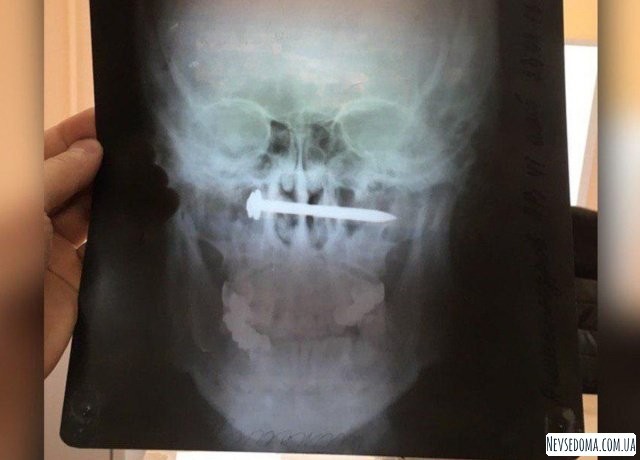

Местный житель поселка Эльбан Амурского района Хабаровского края целых 2 года прожил с гвоздем в голове. Мужик уверяет, что гвоздь поселился в его носоглотке совершенно случайно во время ремонта. Ранение ему показалось недостаточно серьезным, чтобы бить тревогу. Поэтому он помазал рану зеленкой, жил себе дальше и горя не знал. Но потом он заметил, как слух начал снижаться и мужчина решил, что пора бы обратиться к доктору.

В больнице ему сделали рентген-снимок и решили провести операцию по извлечению дюбель-гвоздя. Как сказал врач лор-отделения больницы Александр Карпов, не сам гвоздь нарушил слух, а эрозия крупных кровеносных сосудов и воспаление, которое вызвало нахождение инородного стального предмета в головушке мужчины. Также доктор добавил, что оперативное вмешательство в этом случае могло привести к летальному исходу.

Тем не менее операция прошла успешно, и сейчас пациента готовят к выписке. Гвоздь, скорее всего, мужчина взял на память.